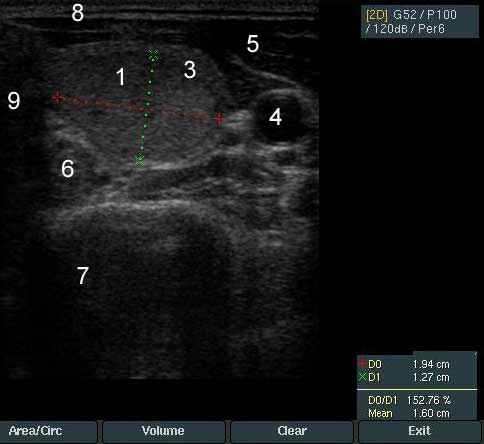

У пациентки 35 лет выявлен узел левой доли щитовидной железы. На снимках цифровые обозначения соответствуют следующим структурам

1. Узел щитовидной железы - Размер узла 1,9 на 1,2 на 2,4 см.

2. Ткань щитовидной железы

3. Ободок узла щитовидной железы (ободок Halo)

4. Сонная артерия

5. Короткие мышцы шеи, которые находятся перед щитовидной железой

6. Пищевод

7. Позвоночник

8. Кожа и подкожно-жировая клетчатка

9. Трахея

Узел по структуре изоэхогенный с четкими контурами и ободком Halo. По данным допплеровского исследования кровоток в узел смешанного типа - перинодулярный и интранодулярный.